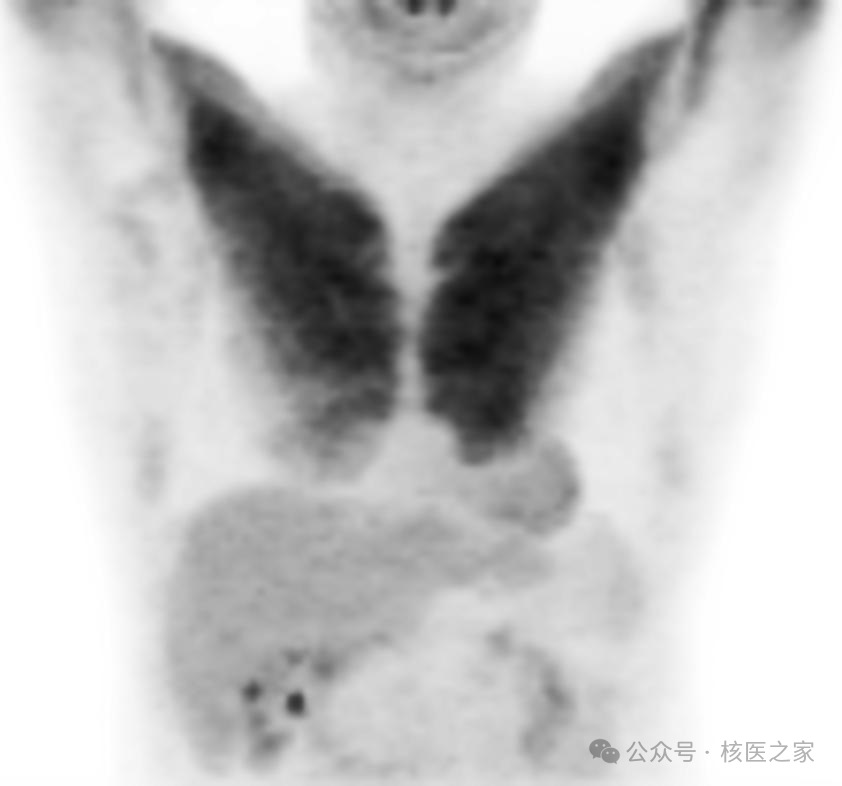

实际上,不同的锻炼部位在PET/CT上一目了然;更有甚者有些健身狂热者6年如一日(图4)!

图4.双侧上肢肌显著摄取FDG(前后6年惊人一致)